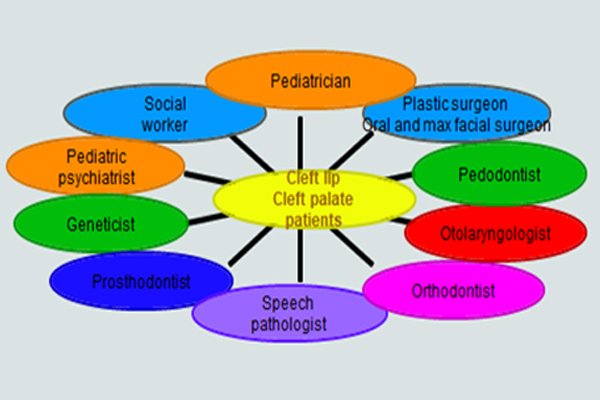

The Patients With clefts Presents a Complex biologic, Sociologic and Psychologic Problem,

One Whose best Management Involves Several Disciplines.

AIM OF REHABILITATION OF CLEFT PALATE PATIENTS IS TO ENABLE HANDICAPPED

INDIVIDUALS TO ASSUME AN EFFECTIVE POSITION IN SOCIETY